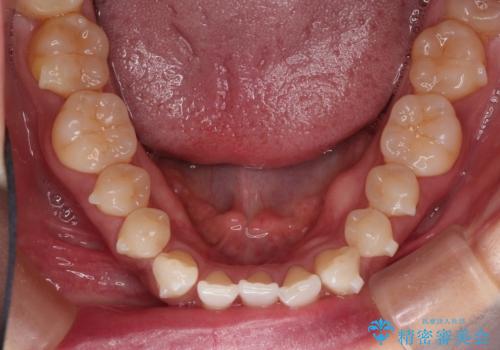

- 上顎の前歯のがたつきと、下の前歯の隙間を主訴に来院されました。

下の前歯が先天的に欠損していました。

上顎の歯と歯の間をわずかに削りスペースを作り、ガタガタの改善し、下顎の前歯は隙間を閉じる計画としました。